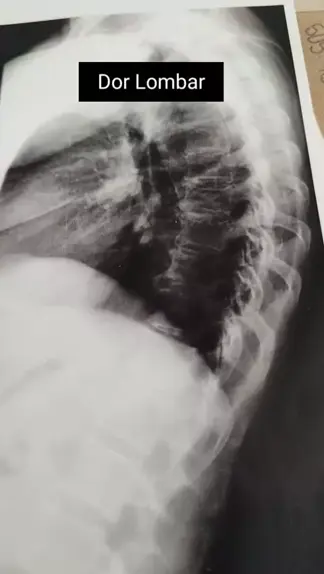

Paciente com dor lombar crônica. A radiografia mostra um ósteófito marginal (bico de papagaio) na região torácica da coluna. O ultrassom mostrou presença de microcalculos que podem causar esse desconforto... #kwai #love #cena